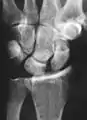

Static scapholunate dissociation